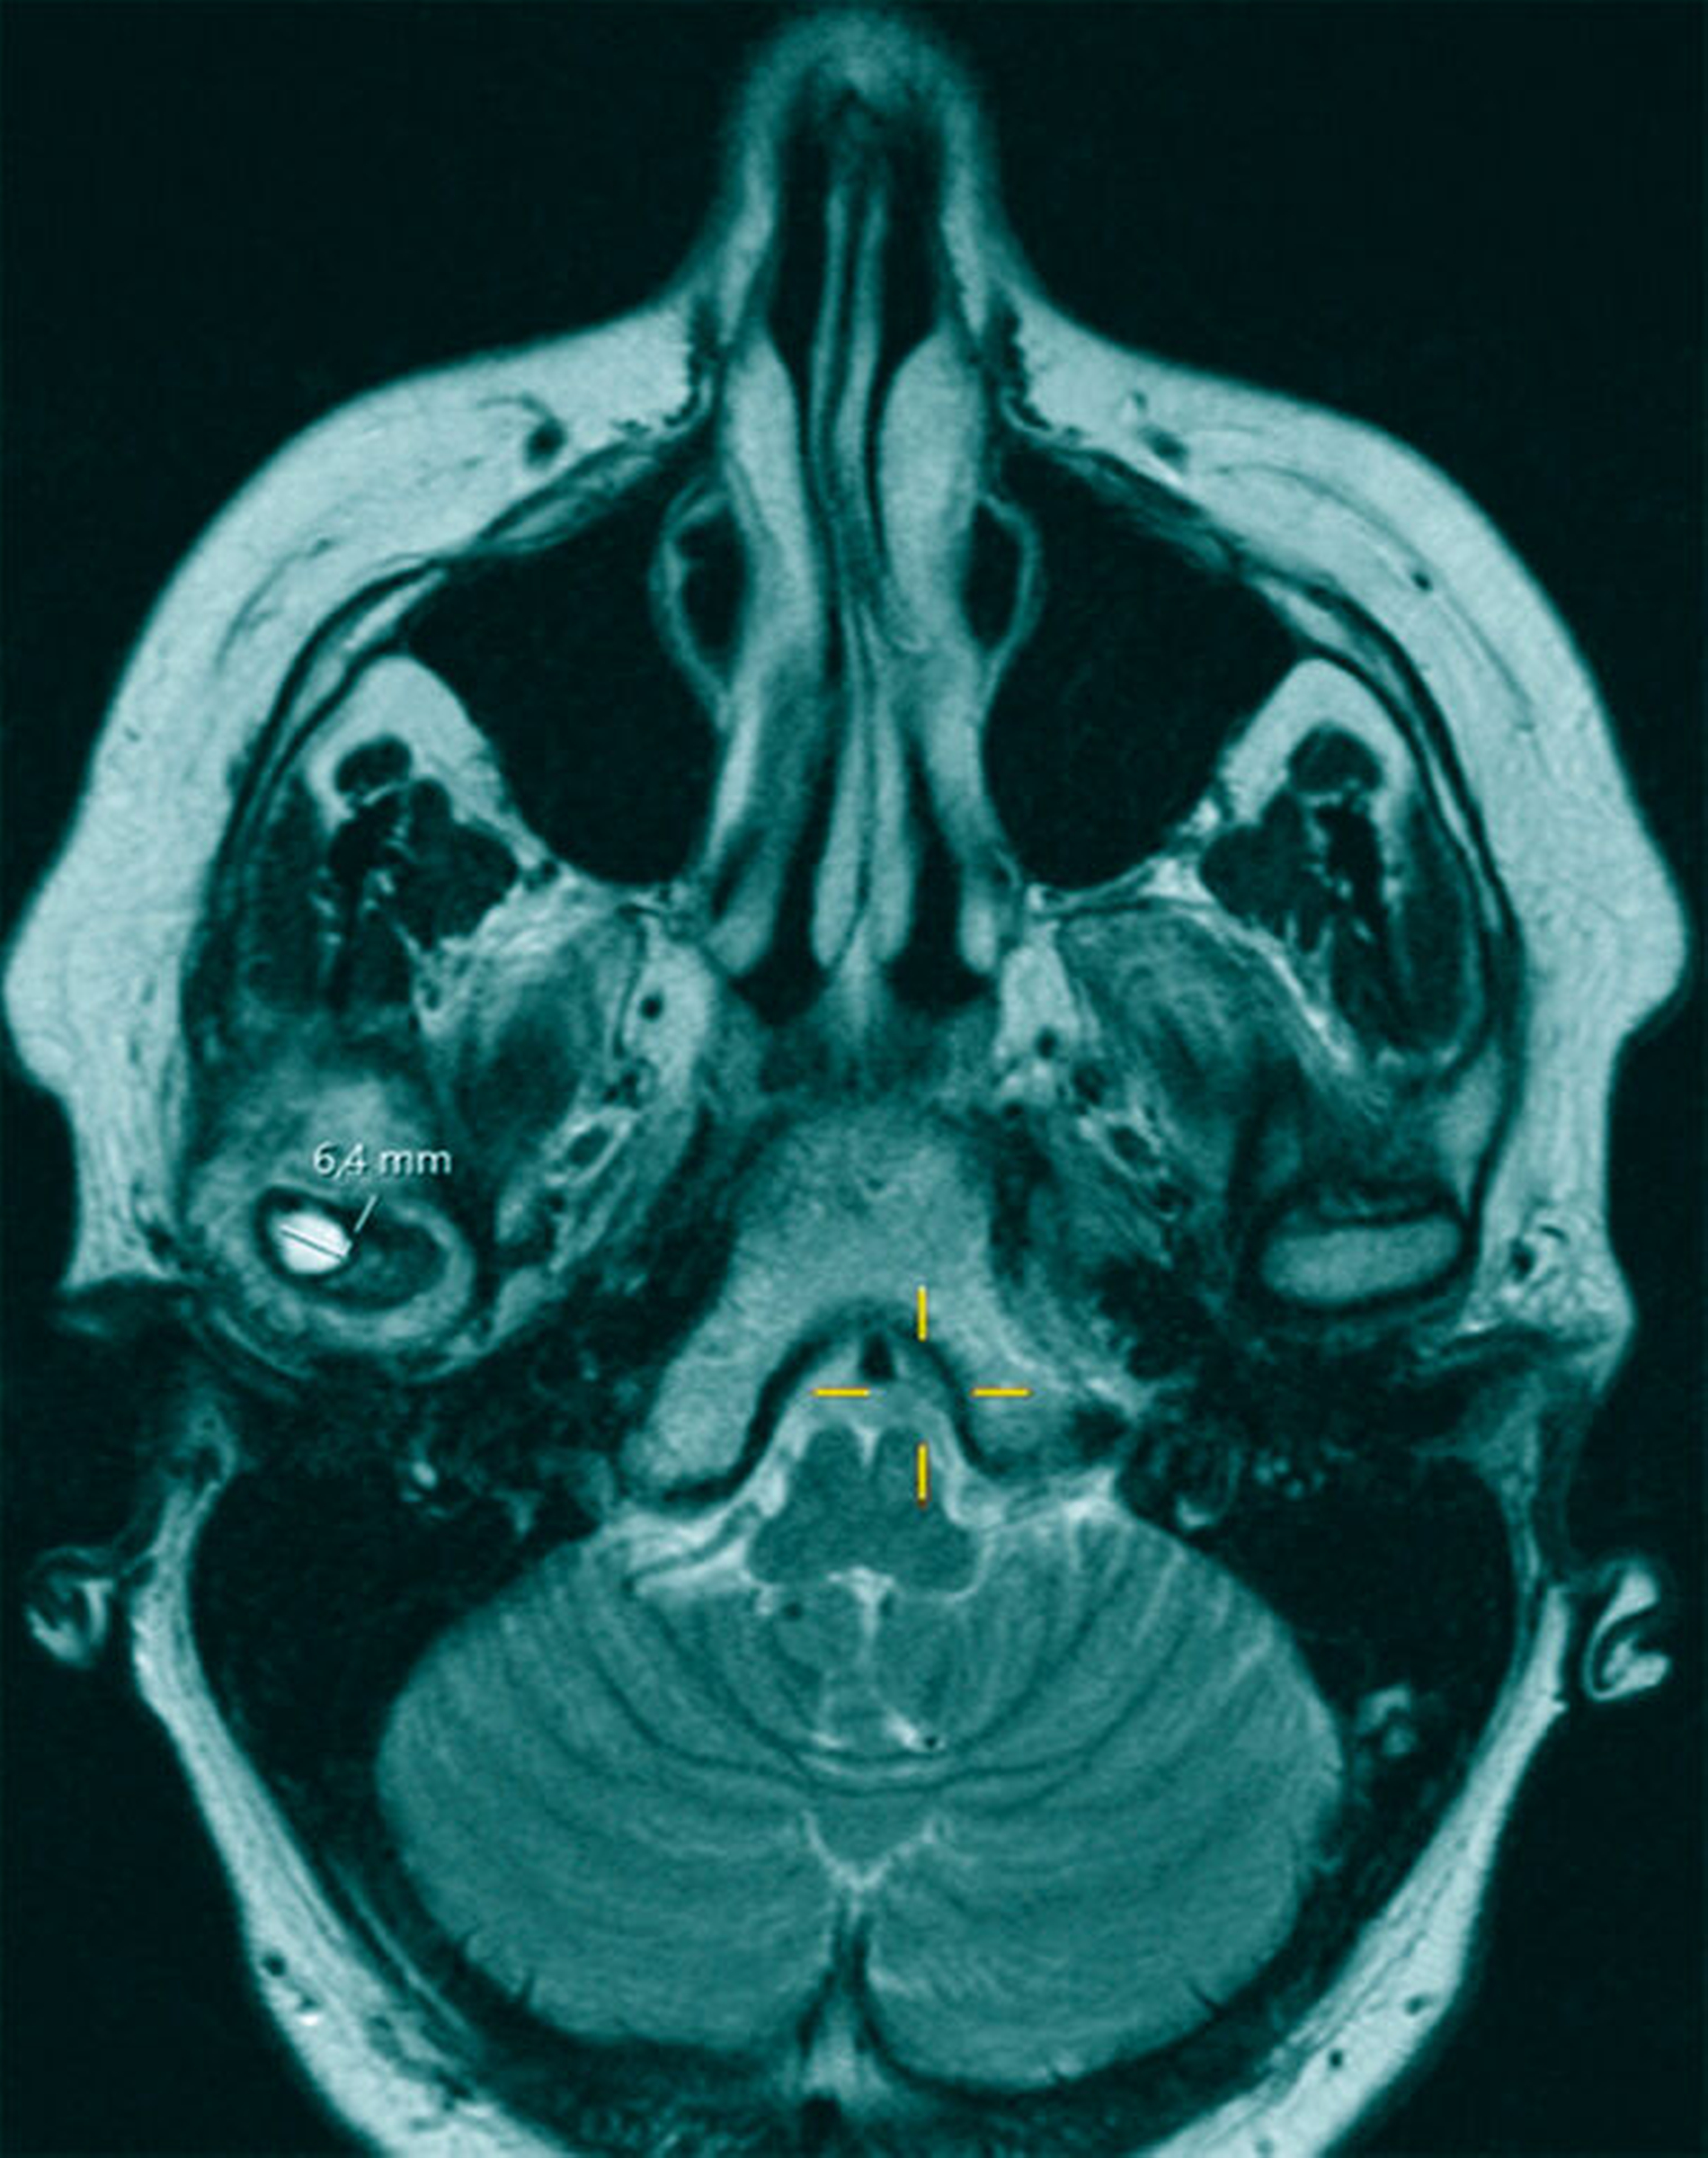

Zur genaueren Eingrenzung und Beurteilung der Knochenstrukturen wurde allerdings eine zusätzliche CT-Untersuchung empfohlen, die im Hinblick auf eine navigationsgestützte Probenentnahme nach kranialem Einbringen von vier Markierungsschrauben durchgeführt wurde. Hierbei wiederum ergab sich in Korrelation mit der bereits durchgeführten MRT-Untersuchung eine Mehrsklerosierung des Capitulums rechts mit geringen Arrosionen im apikalen Anteil und einer glatt begrenzten Zyste. Somit wurde von den radiologischen Kollegen die Verdachtsdiagnose eines Chondrosarkoms aufgestellt (Abbildung 2).